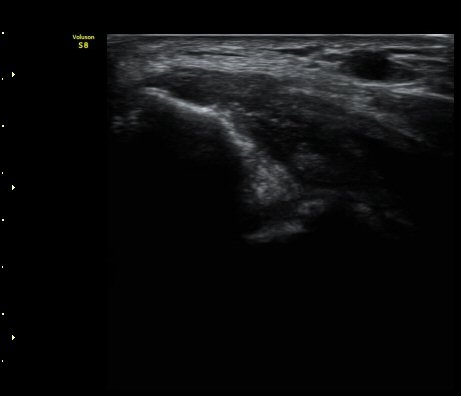

ÃÊÀ½ÆÄ °Ë»ç

³»»ó°ú¿¡¼­ ¼Õ¸ñ±¼°î°Ç Á¾´Ü¸é°Ë»ç»ó ³»¤µ¾Æ°ú ÇÇÁú°ñÀÇ ºÒ±ÔÄ¢º¯È­¿Í ÈûÁÙ³» ¿¬°á¼º

¼Ò½Ç ¹× Àü¹ÝÀûÀÎ Àú¿¡ÄÚ ºÎÁ¾ÀÌ °üÂûµÈ´Ù(±×¸² 1, 2, 3). ±¼°î°Ç ÀϺδ Á¤»óÀûÀÎ °í¿¡ÄÚ

¼¶À¯ ¾ç»óÀ¸·Î °üÂûµÈ´Ù(±×¸² 4). ÈûÁ٠Ⱦ´Ü¸é °Ë»ç¿¡¼­µµ °Ç³» ¿¬°á¼º ¼Ò½Ç°ú Àú¿¡ÄÚ

º¯È­°¡ °üÂûµÈ´Ù(±×¸² 5).  ÃÊÀ½ÆÄÀ¯µµÇÏ ÁÖ»ç ½Ã ÁÖ»ç¾×ÀÌ °Ç³»¿¡¼­ ÀÚÀ¯·Ó°Ô ÆÛÁ®¼­

°ÇÀÇ ½ÉÇÑ ÆÄ¿­À» º¸¿©ÁØ´Ù(÷ºÎ ÆÄÀÏ µ¿¿µ»ó 1).